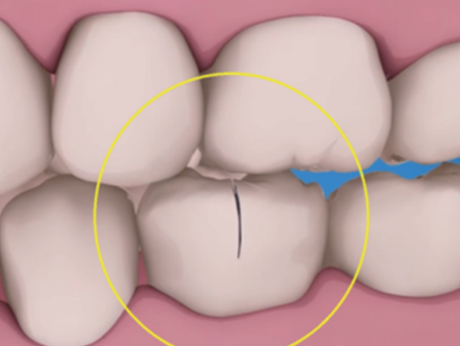

신경제거 후 신경으로부터 받던 영양분을 공급받지 못해 약해진 치아는 작은 충격에도 금이 가거나, 부러지거나, 깨져버리기 때문에 단단한 크라운을 씌워 치아를 보호해야 합니다.